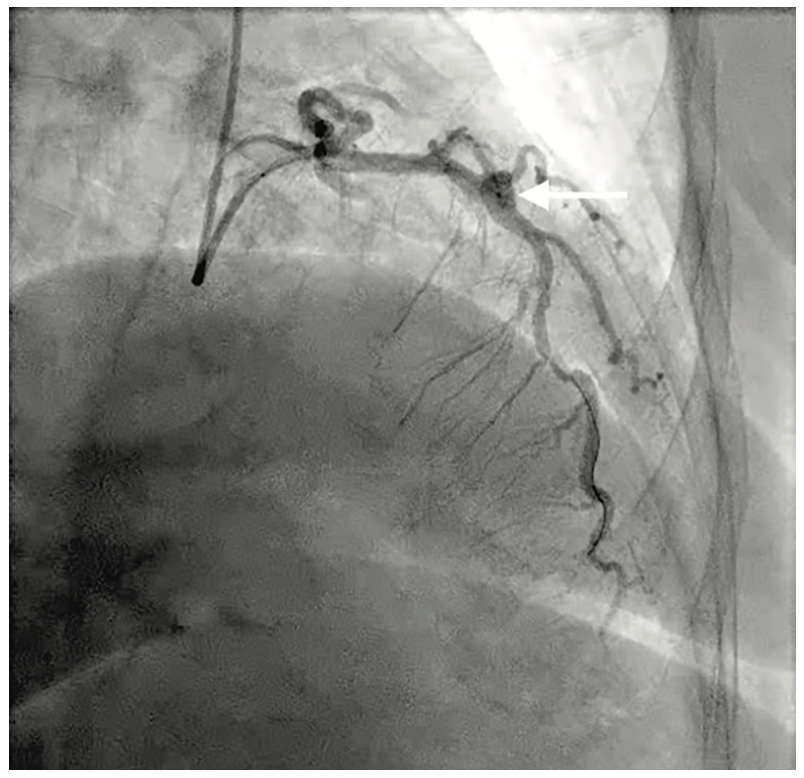

A 69-year-old woman with history of hypertension, paroxysmal atrial fibrillation, coronary artery disease, non-insulin dependent type II diabetes and hyperlipidemia presented with one-week history of chest tightness associated with worsening dyspnea on exertion. She had previously presented with non-ST segment elevation myocardial infarction 6 months earlier, requiring placement of a single 4 x 24 mm Synergy DES (Boston Scientific) in the mid LAD (Figure 1) and subsequent OCT imaging (Abbott) demonstrating adequate stent expansion and apposition (Figure 2). Electrocardiogram on current presentation revealed T wave changes in anterolateral leads and cardiac biomarkers were noted to be significantly elevated.

Coronary angiography, via right radial artery access, revealed a large LAD with a patent mid stent with native coronary ectasia and saccular aneurysm formation around the stented segment (Figure 3). The remainder of the coronaries were unremarkable. A 6 French XB 3.0 guide (Medtronic) was used to selectively engage the left main coronary artery. A Samurai guidewire (Boston Scientific) was advanced across the LAD stent into the apical segment. OCT imaging of the mid LAD confirmed adequate apposition of the stent at the distal and proximal segments, with significant ectasia and malapposition in the aneurysmal mid segment of the vessel around the stent (Figure 4). No further intervention was performed at that setting. These findings were discussed with the patient and the primary team, along with cardiothoracic surgery, upon patient recovery. Treatment options, specifically surgical ligation of the LAD with coronary artery bypass grafting to the LAD and diagonal branches, a percutaneous approach with covered stent placement in the mid LAD to exclude the aneurysm, and a conservative medical therapy approach were deliberated. The patient firmly refused surgical intervention after understanding the risks and benefits of all the treatment options offered to her. Conservative medical therapy was deemed inappropriate in this setting of myocardial infarction.